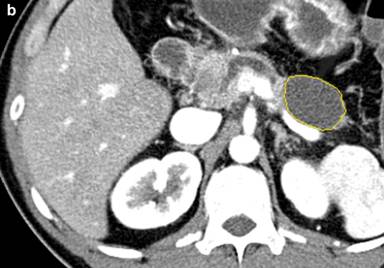

For measurement of the cyst diameter and volume, commercially available software (CT Oncology; Siemens Medical Solutions) was used on an image-processing workstation (Leonardo Workstation, syngo® 2008A MultiModality Workplace (VE26A) platform; Siemens Healthcare, Erlangen, Germany). Two independent investigators (H.C. and P.R.) with one and two years of experience using the software, respectively, performed the measurement on pancreatic parenchymal phase images. Pancreatic parenchymal phase was selected due to the superior conspicuity of the lesions in this phase. The application of this software in the volumetric measurement of abdominal masses has been described previously [13, 18]. The graphic user interface is divided into 4 screens: axial, coronal, sagittal and 3D views. Once the investigator identifies the pancreatic mass by drawing an approximate line across it, the software selects the entire lesion. This is achieved by three-dimensional reasoning by the software to remove neighboring normal pancreatic tissue, hence, generating a volume of interest around the drawn line and extends the segmentation on the basis of histogram analysis within the generated volume on interest (Figure 2). The selections can be edited by the investigator in x, y, and z planes, if necessary.

Figure 2. Coronal (a.), axial (b.), sagittal (c.) and three dimensional (d.) CT images of a histopathologically proven pancreatic tail mucinous cystic neoplasm in a 39-year-old man. Despite a dilated pancreatic duct no connection was visualized on endoscopic ultrasound with the cyst. Borders of cyst are marked with yellow line by the software. CT volumetry (22.3 mL) and an elongation value (0.67) for the cyst were automatically generated by the software once the measurement was finalized by the observer. Pancreatic head cyst was not segmented because of apparent connection with the pancreatic duct that was dilated. Also, note that the patient was a male with mucinous cystic neoplasm, an extremely rare occurrence. |